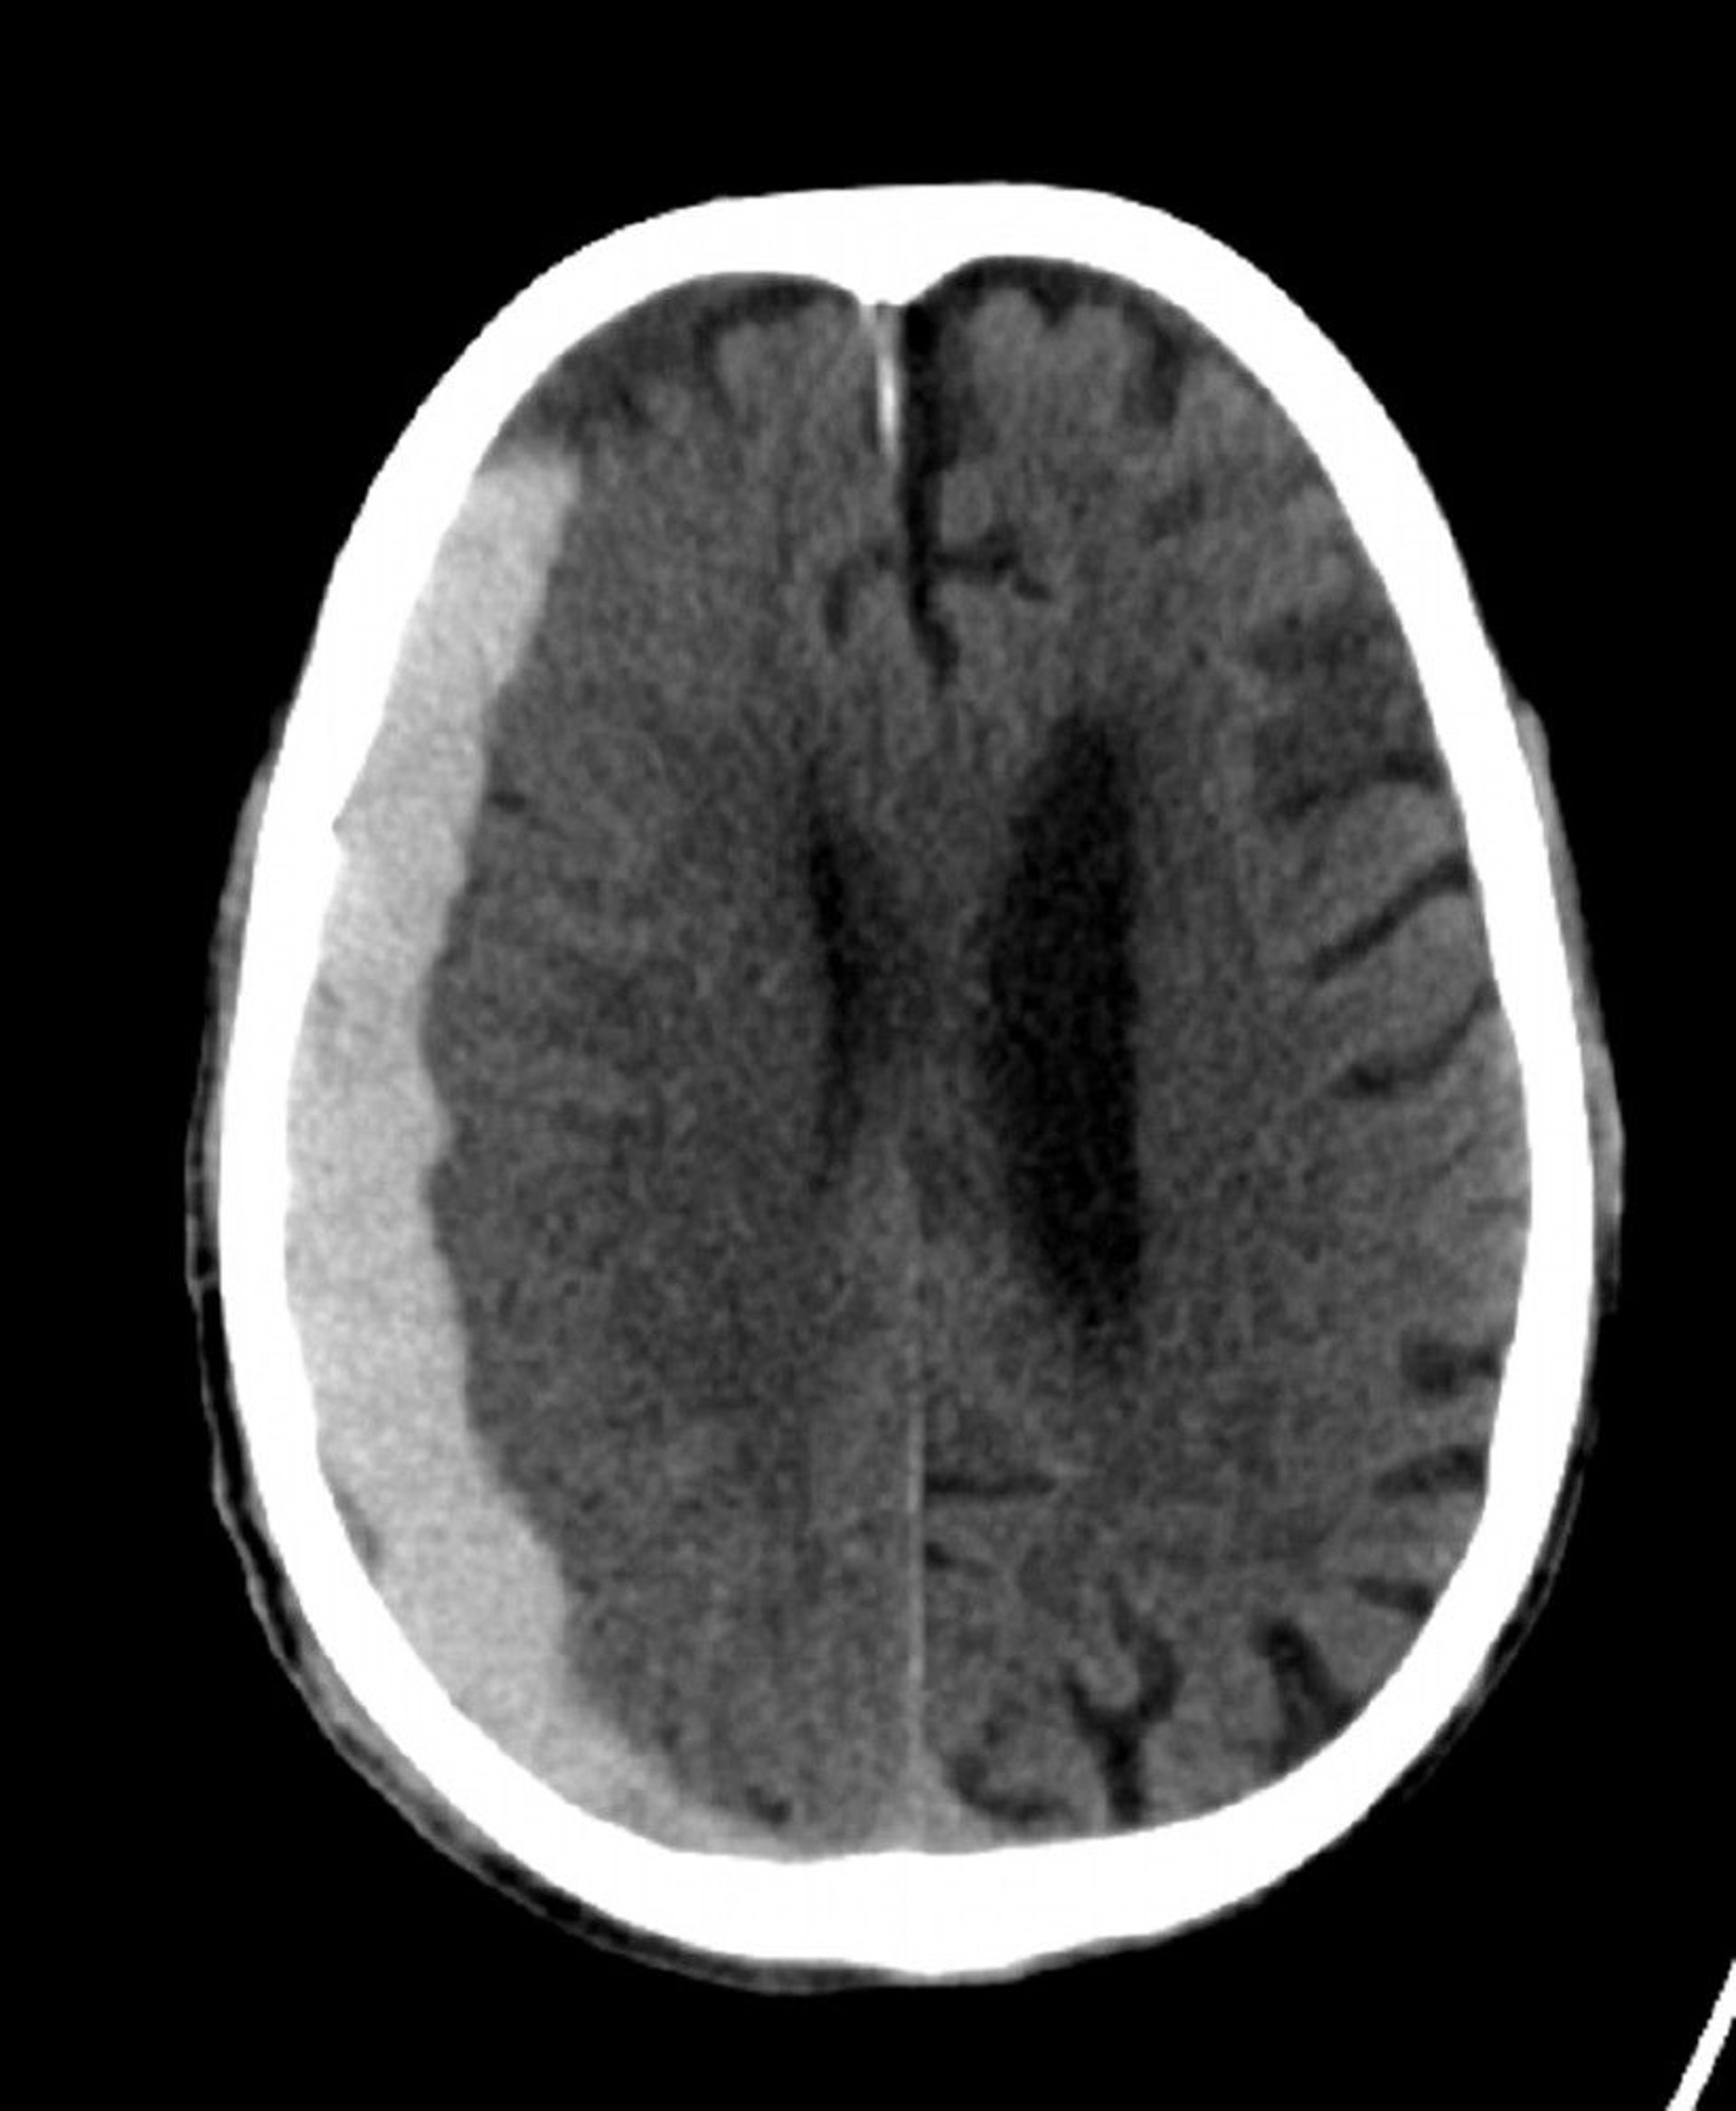

Subdural Hemorrhage (CT)

Classic crescent-shaped hyperdensity extending across suture lines.